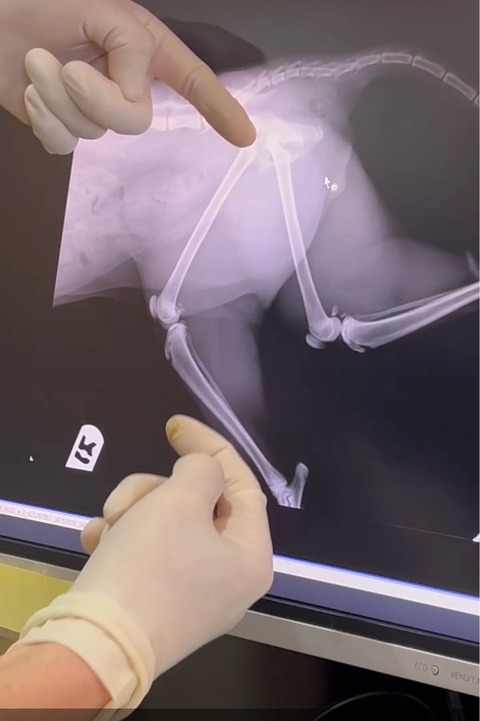

やはり 骨折ですね。。。

骨折して完全にズレています

今後 チャト君の様に排便、

排尿障害が出なければ良いのですが、

日曜日には手術になる予定です。